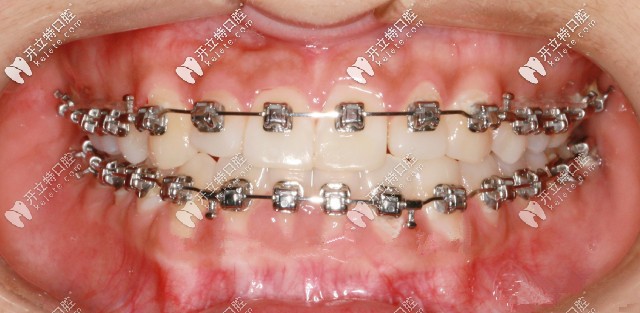

先戴頜墊再做矯正

此案例是戴頜墊3個(gè)月左右,解除反頜后開(kāi)在粘接托槽